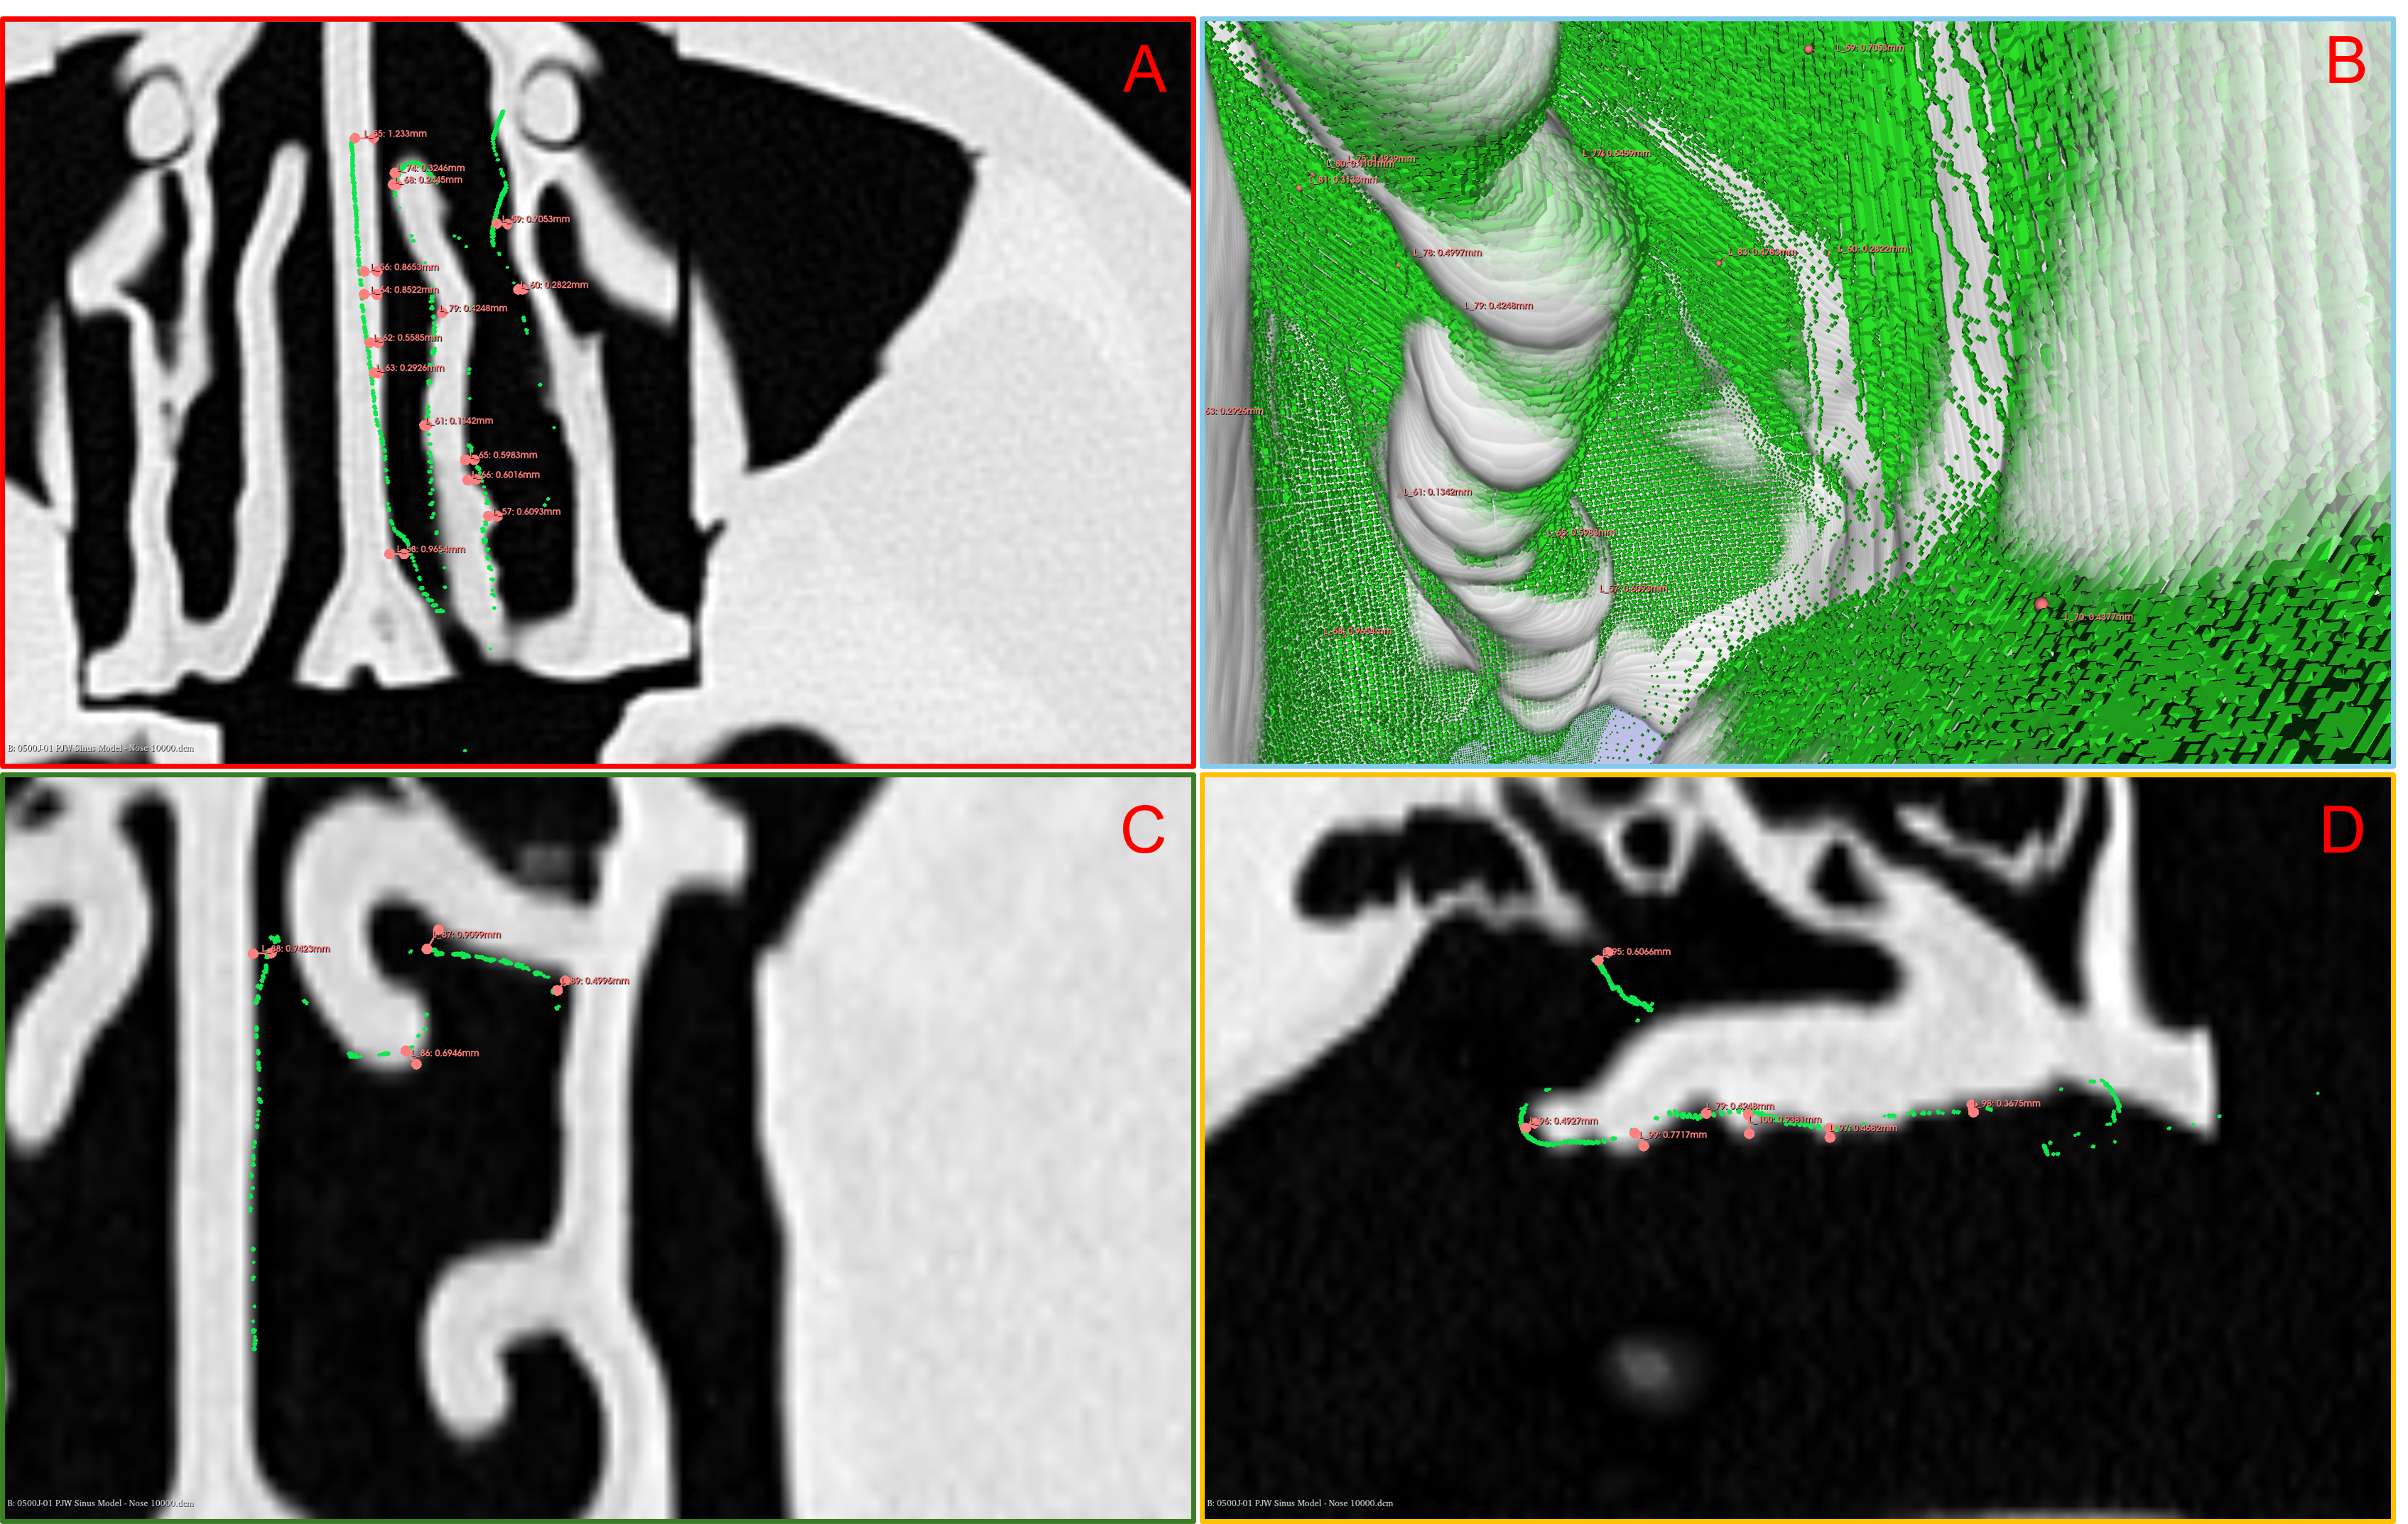

In this section, we manually registered the 3D reconstruction results with the CT model and employed the measurement tools integrated within 3D Slicer to assess their accuracy. The superimposition of the 3D reconstruction and CT model is depicted in Figure 3 B. The green mesh represents the endoscopic 3D reconstruction, while the white mesh corresponds to the CT model. The alignment between the white and green meshes demonstrates a high degree of structural fidelity in our 3D reconstruction. To quantitatively evaluate the accuracy of our reconstruction, we manually measured the spatial distances between the endoscopic 3D reconstruction and corresponding points in the CT data. In the 2D view, we specifically selected regions exhibiting the largest deviations as well as those with average deviations, as illustrated in Figure 3 A, C, and D.

Upon conducting distance measurements within the sectional view, we determined that the majority of points attained reconstruction errors less than 1mm, with the maximum recorded error less than 2 mm. These findings verify that the accuracy of our algorithm substantially surpasses that of the current SOTA methodologies[18].

Figure 3: Comparison between 3D reconstruction and CT model. Figure 3B displays the 3D reconstruction’s green mesh aligned with the CT model’s white mesh. Additional figures A, C, and D show the 3D reconstruction and CT model alignment from different fixed viewpoints.